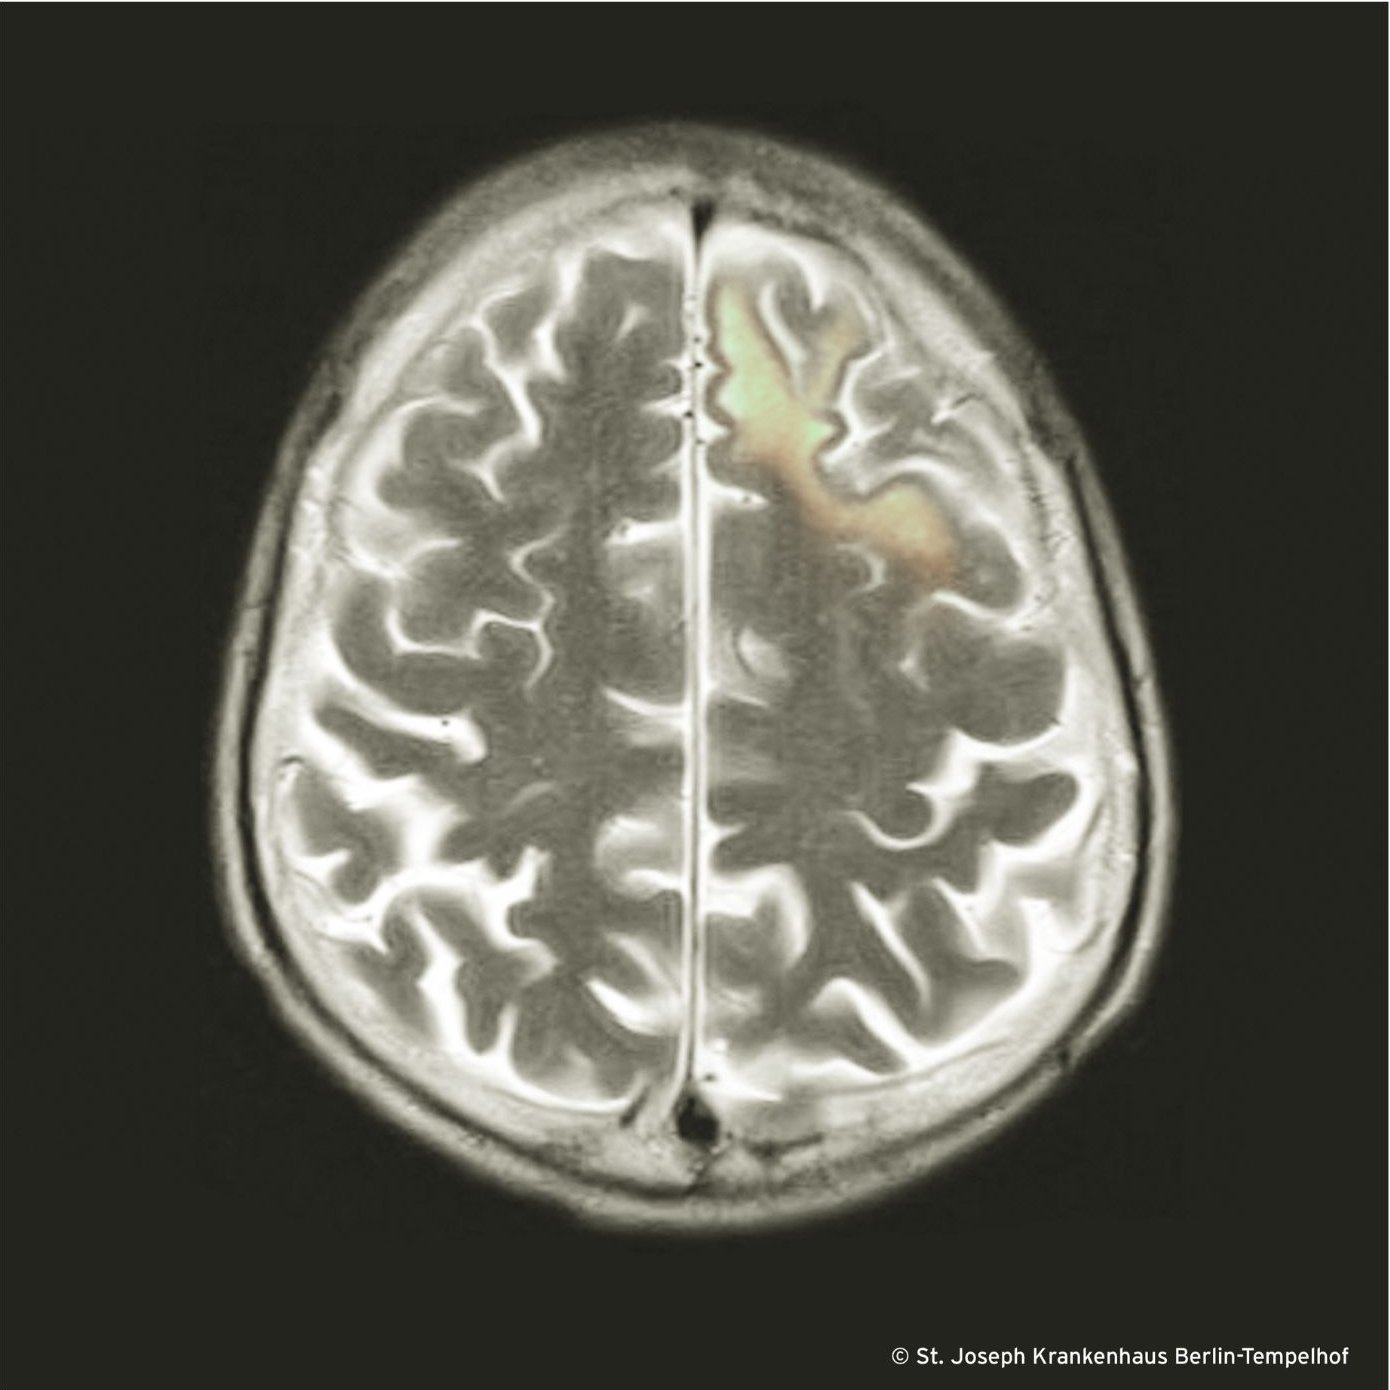

Nicht jede JCPyV-Infektion sieht so aus wie die klassische PML auf unserem Bild mit asymmmetrischen (multifokalen) subkortikal lokalisierten T2-Hyperintensitäten ohne Hinweise auf Oedem, Raumforderung und (in aller Regel) ohne Kontrastmittelanreicherung.